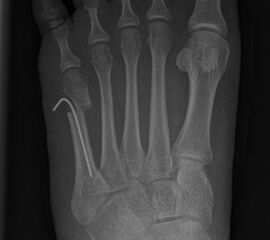

Abb. 39 a-b: Minimalinvasive Krallenzehenkorrektur mit präoperativen und intraoperativen Röntgenaufnahmen (a) und klinischem Bild prä- und postoperativ (b).

Zum Lesen der Bildbeschreibung und zur Vollansicht bitte die Bilder anklicken. Bilder: A. Helmers.